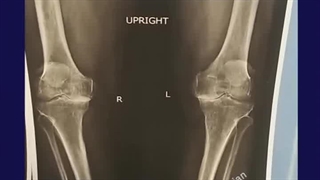

درگیری شدید ساییدگی زانو و به دنبال آن درد بسیار زیاد بیمار منجر به تصمیم انجام جراحی برای بیمار شد، که باهم در این ویدیو می‌بینیم.